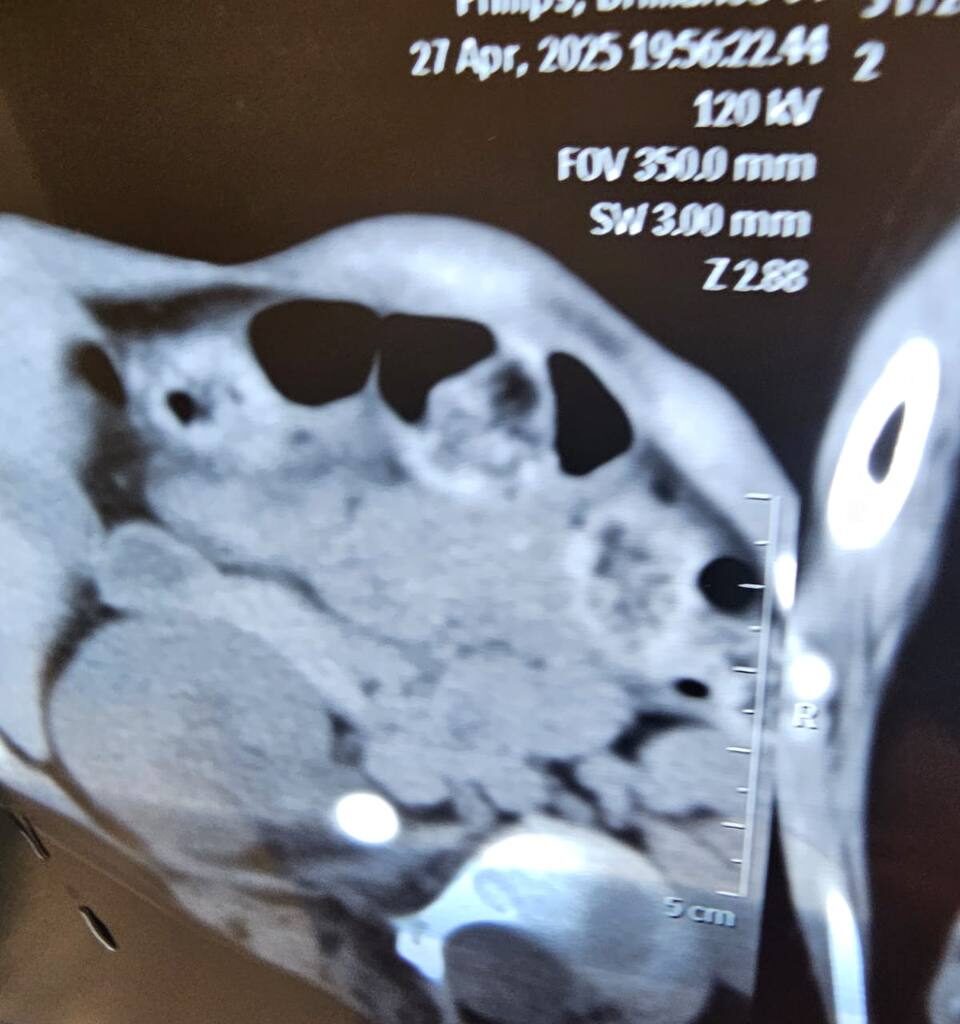

الطفلة، التي وُلدت بانحراف حاد في العمود الفقري، وتشوهات في القفص الصدري، وضعف في عضلة القلب، وكسل في عضلات الحنجرة، فضلاً عن تلف دماغي سبّب التهابات تنفسية متكررة وصعوبات كبيرة في التخدير، تبيّن بعد الفحوصات الدقيقة وجود حصاة بحجم 2 سم في الكلية اليسرى، ما استدعى تدخلاً جراحيًا عاجلًا وحذرًا في آنٍ واحد.

تحت إشراف الجراح المتخصص الدكتور يحيى الخفاجي، أُجريت عملية رفع الحصاة باستخدام تقنية المنظار عبر فتحة لا تتجاوز 1 سم، في إجراء يُعدّ تحديًا حقيقيًا في ظل هشاشة الحالة الصحية وتعقيدها. وقد جرت العملية بنجاح لافت، دون مضاعفات، وسط تنسيق دقيق بين الفرق الطبية المختلفة.